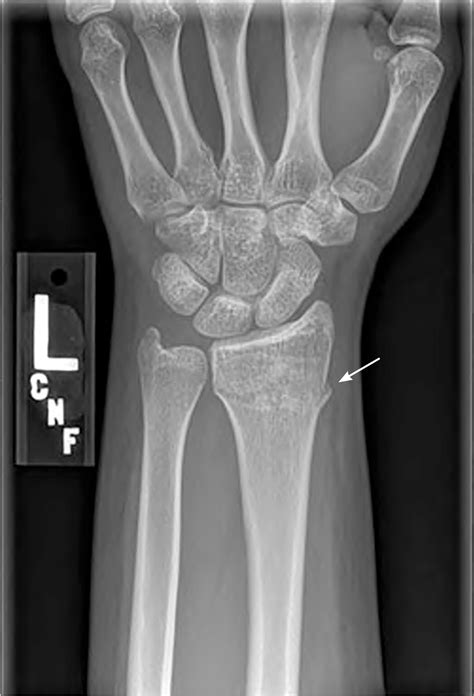

Diagnosing an Ulnar Styloid Fracture

Diagnosing an ulnar styloid fracture typically involves a combination of physical examination and imaging tests. The diagnostic process may include:

• Physical Examination: A healthcare provider will assess the wrist for pain, swelling, and deformity. They may also check the range of motion and stability of the wrist.

• X-rays: These are the primary imaging tool used to confirm the diagnosis. X-rays can show the location and extent of the fracture.